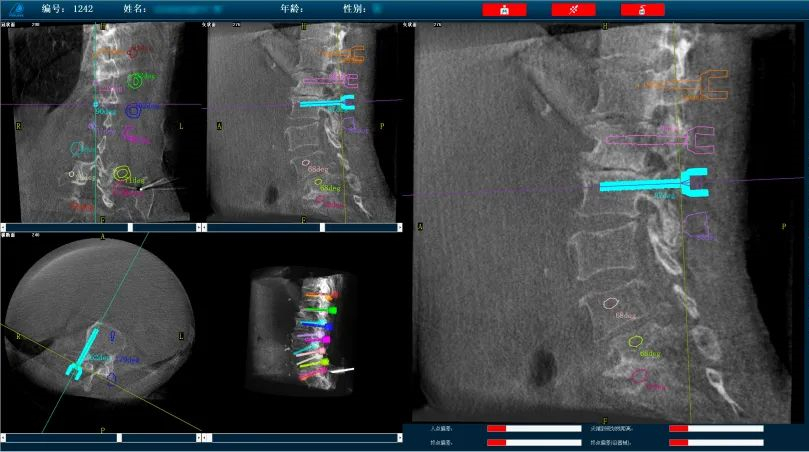

而外科手術(shù)機(jī)器人與三維C形臂配合,基于3D影像數(shù)據(jù),利用手術(shù)規(guī)劃軟件,術(shù)前模擬植入物狀態(tài),引導(dǎo)醫(yī)生進(jìn)行預(yù)手術(shù)規(guī)劃,輔助評(píng)估和及時(shí)調(diào)整手術(shù)路徑規(guī)劃設(shè)計(jì),機(jī)械臂準(zhǔn)確運(yùn)動(dòng)到規(guī)劃位置,借助導(dǎo)向套筒,為醫(yī)生提供穩(wěn)定的導(dǎo)針置入路徑。外科手術(shù)機(jī)器人以實(shí)現(xiàn)準(zhǔn)確、微創(chuàng)手術(shù)為首要目標(biāo),通過手術(shù)機(jī)器人準(zhǔn)確定位可以減小患者手術(shù)過程中的開口大小,減少神經(jīng)損傷風(fēng)險(xiǎn),實(shí)現(xiàn)手術(shù)操作的準(zhǔn)確度和安全性。

普愛醫(yī)療骨科手術(shù)機(jī)器人可廣泛地應(yīng)用于多節(jié)段脊柱外科手術(shù),輔助醫(yī)生定位病灶部位,為脊柱外科手術(shù)(經(jīng)皮椎體成形術(shù)、椎弓根螺釘內(nèi)固定術(shù)等術(shù)式))提供術(shù)前手術(shù)流程規(guī)劃、入釘位置、角度可視化引導(dǎo),模擬仿真入釘輔助。產(chǎn)品優(yōu)勢(shì)特點(diǎn)如下:

復(fù)雜手術(shù)標(biāo)準(zhǔn)化:直觀的軟件操作界面引導(dǎo),減少手術(shù)中的不確定環(huán)節(jié),使得復(fù)雜手術(shù)流程標(biāo)準(zhǔn)化,讓從業(yè)經(jīng)驗(yàn)不足的醫(yī)生也能快速掌握,縮短醫(yī)生的學(xué)習(xí)曲線。